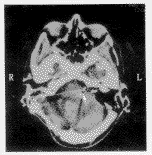

图1 例1患者术中EABR

7例患者术中均能找到Luschka孔而插入ABI电极,其中6例能记录到典型的EABR(图1),即出现2个正波(P1和P2),并且当刺激波极性颠倒时其波形不改变;另1例患者在术中虽经多次更换电极位置仍未能记录到典型的EABR,此患者在术后调配时未能产生有意义的听觉。本组患者术后无颅内感染、脑脊液漏及皮瓣坏死等并发症。术后6周CT检查显示电极位置良好,无移位现象(图2)。

术中电生理监护对电极的正确放置非常重要,面神经和舌咽神经肌电图监护除了对定位Luschka孔有重要帮助外,还能保证术中启动ABI装置时不会同时激发面神经和舌咽神经的肌电活动。术中EABR监护能确定ABI刺激是否激活了听觉通道。典型的EABR由2个或3个正波(P1,P2或P3)组成。理论上讲,直接刺激耳蜗核将诱发出相当于听觉脑干诱发电位的III、IV、V波。在本组病例中仅能记录到2个正波,并且P1和P2的间期提示P2位于IV波的位置,这个结果与Waring[6]的观察一致。有关EABR波形与术后言语识别能力的关系值得进一步探讨。